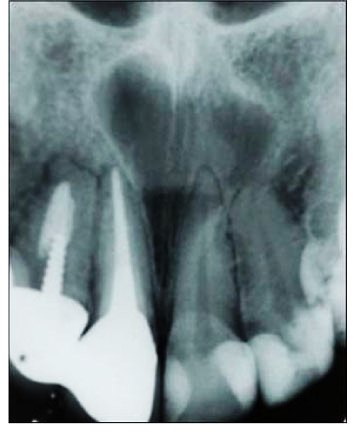

Radiograficamente se apresenta como lesão rediolúcida multicolulada, apresentando aspecto de bolhas de sabão quando as loculações são grandes, ou como favo de mel, quando pequenas. As margens são usualmente, bem definidas. Costumam apresentar reabsorção radicular e expansão da tábua óssea e até perfuração da cortical.

AMELOBLASTOMA UNICÍSTICO

Neste tipo de tumor, o ameloblastoma se desenvolve associado a um cisto.